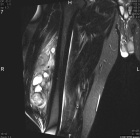

46 year old male noted some fullness in his right thigh about 5 months prior to presentation. Noticed some tense feelings in his thigh over the past month.

Zoom image: Radiological image Radiological image.